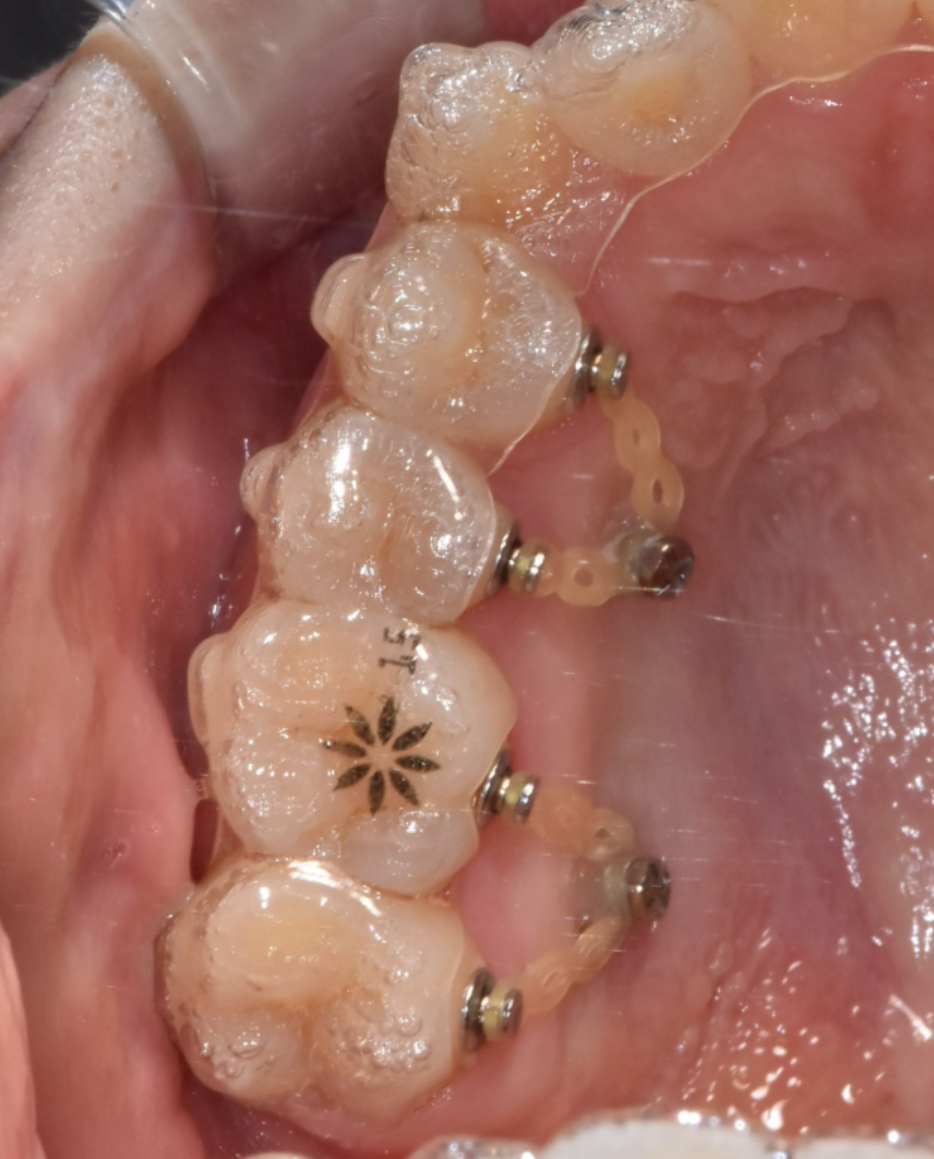

230427

스크류 통증 정도, 얼마나 아플까요?

뼈에 작은 나사를 박는다고 하니

많은 분들이 걱정하시는데요.

마취 후 진행하기 때문에 시술 자체는 통증 없이 진행됩니다.

시술 시간도 굉장히 짧고요.